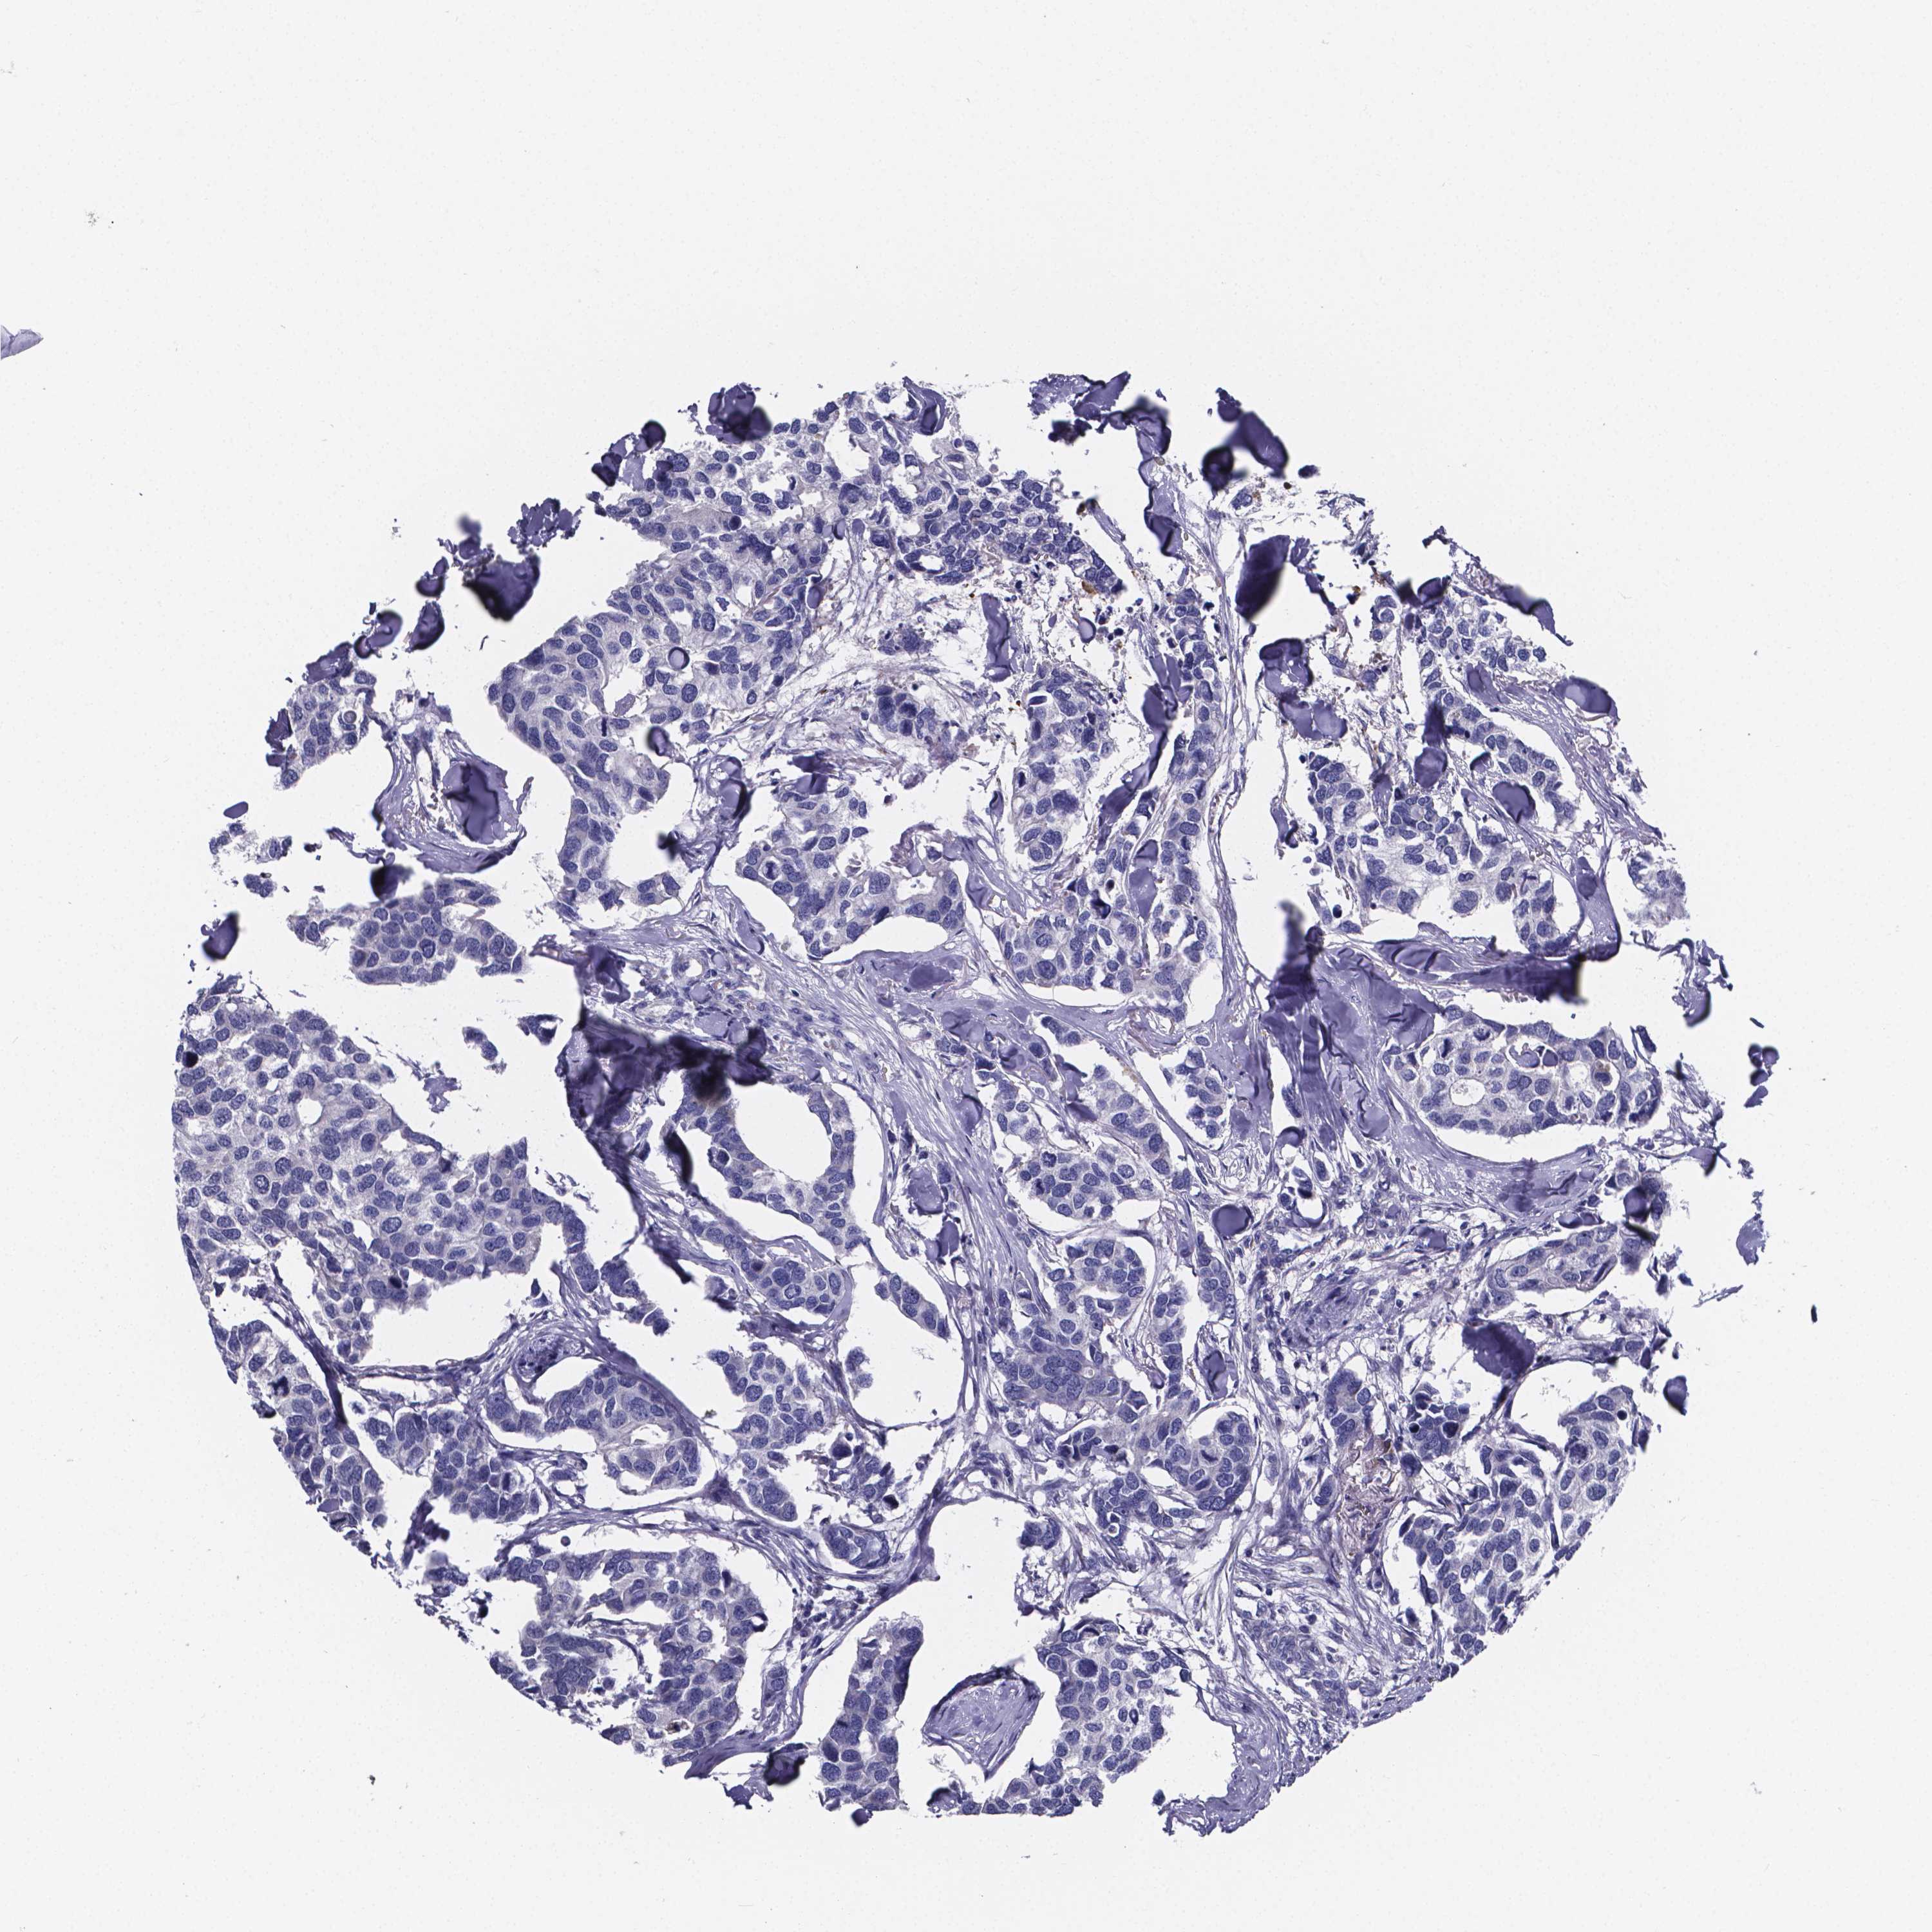

BRCA TCGA BRCA VALIDATION PROTEIN EXPRESSION